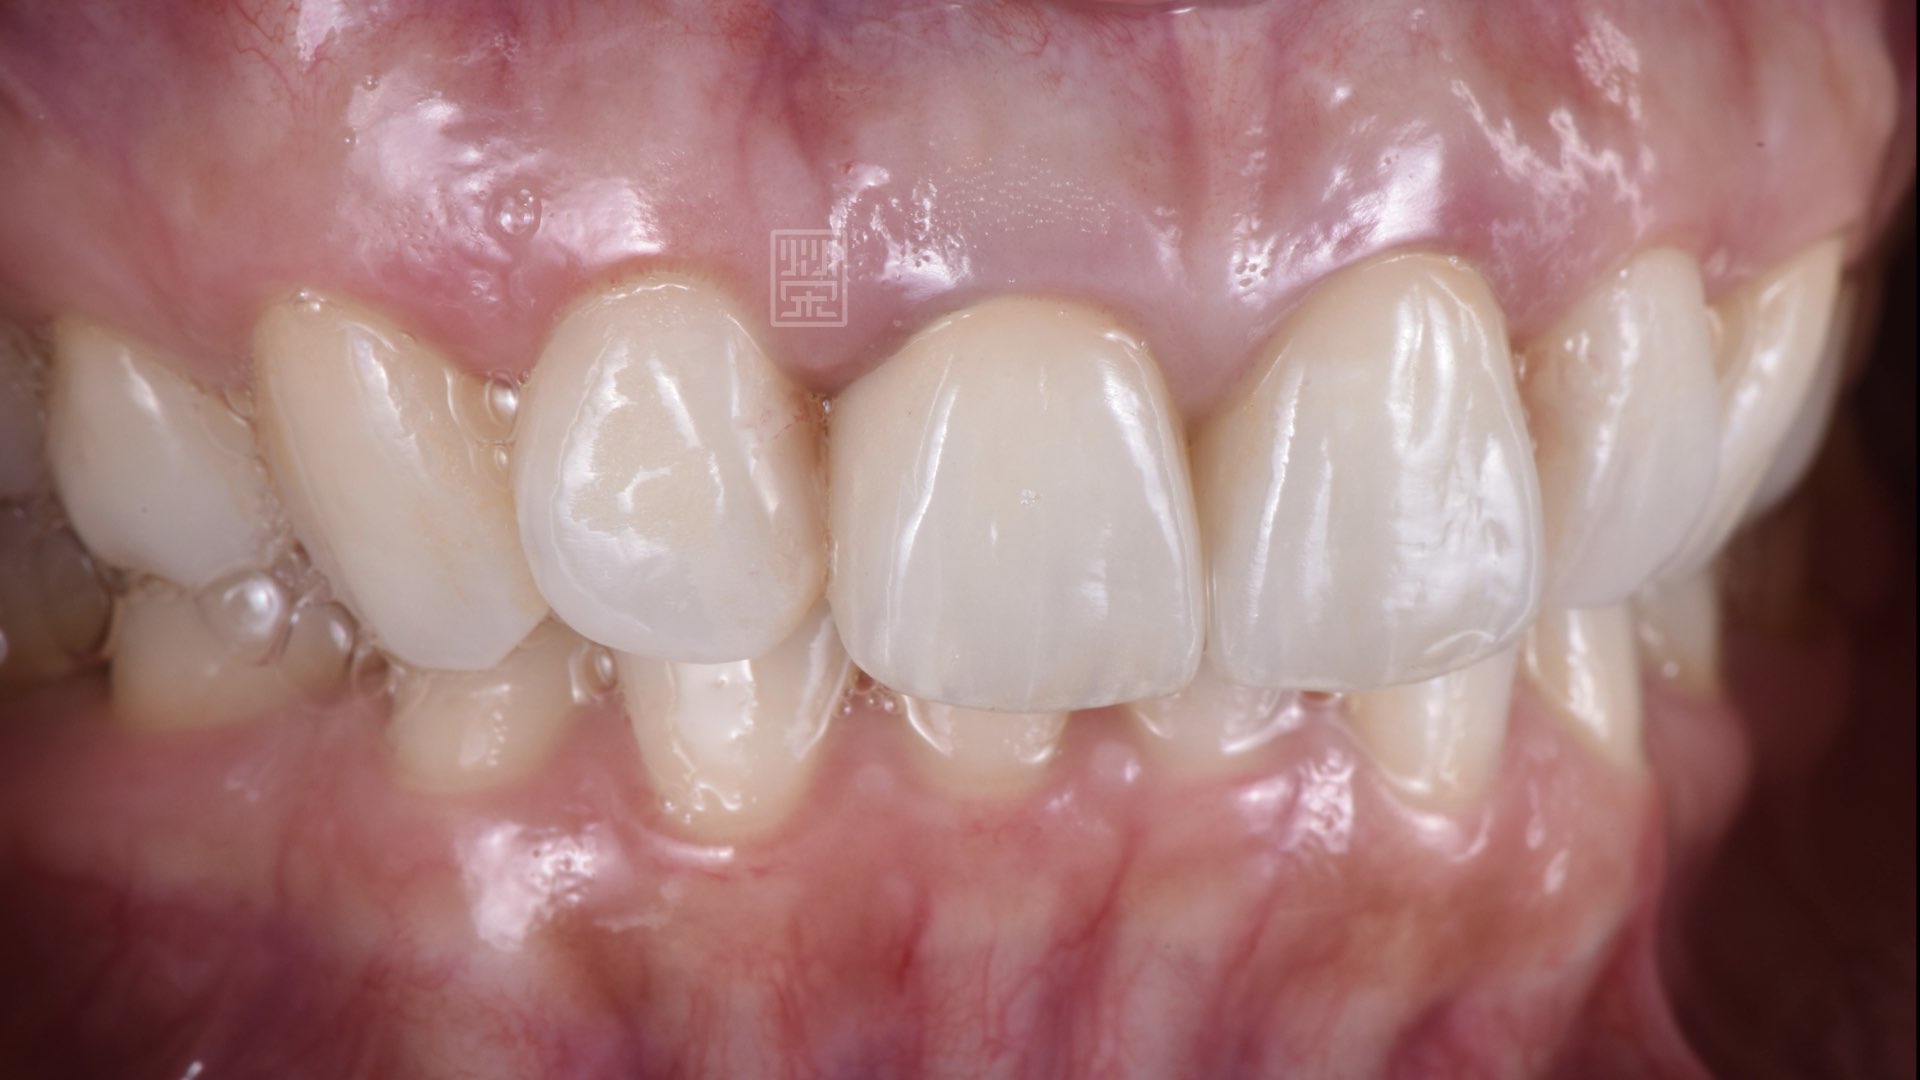

全瓷冠完成